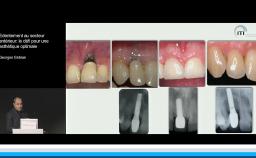

Evaluation du risque esthétique en implantologie orale maxillaire antérieure unitaire

La présentation s’attache à détailler en quoi l’implantation en zone esthétique constitue un challenge lorsqu’il s’agit de réhabiliter la fonction sans oublier de rétablir l’esthétique. A travers quelques cas cliniques, le Dr Eycken s’appuie sur la classification SAC de l’ITI pour évaluer la complexité du cas et y apporter la solution thérapeutique adaptée. Il revient également sur l’importance du positionnement de l’implant dans les 3 sens de l’espace et sur la qualité des tissus mous environnants.